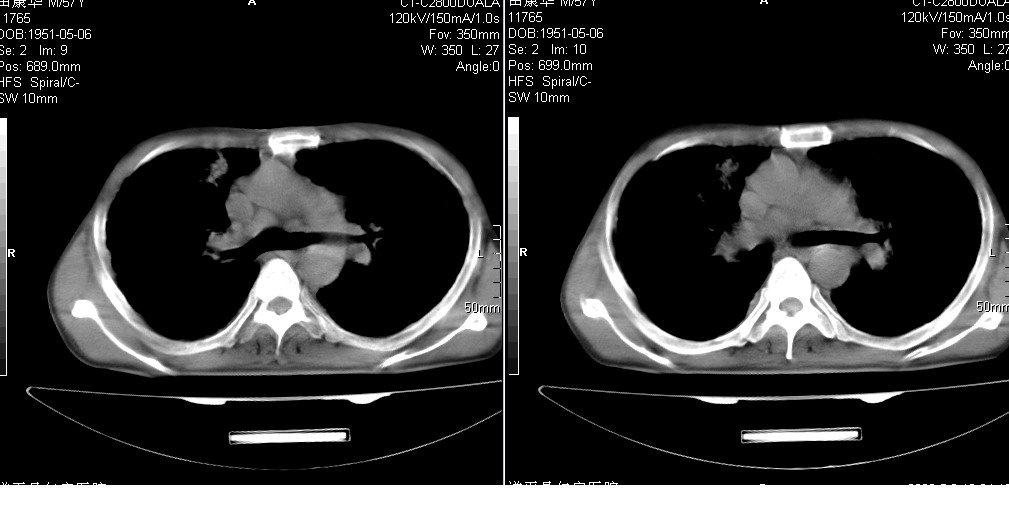

以下是引用光线在2008-5-6 18:36:00的发言:[br]双肺结核(左上肺空洞形成)、间质性改变合并感染,右肺大泡;右侧胸膜增厚。

以下是引用zsl6918在2008-5-7 1:54:00的发言:[br]首先肺泡蛋白质沉着症,其次考虑机遇性感染。